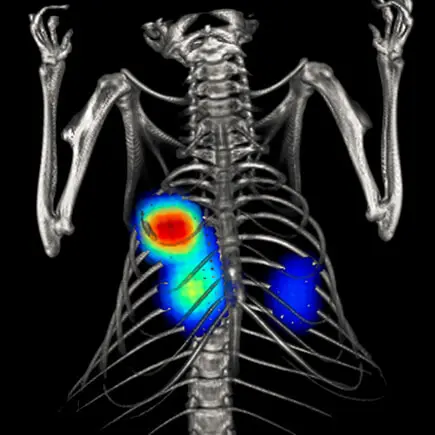

Metastaza nowotworu, znakowanie bioluminescencyjne: IVIS Spectrum CT